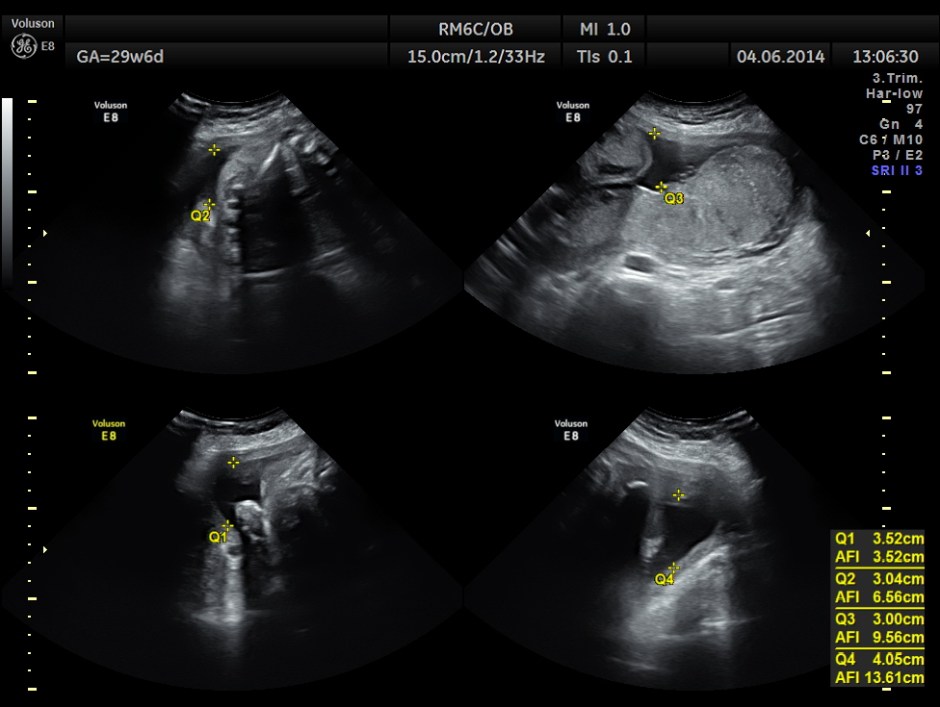

AFI appeared to be normal.

AFI is normal .